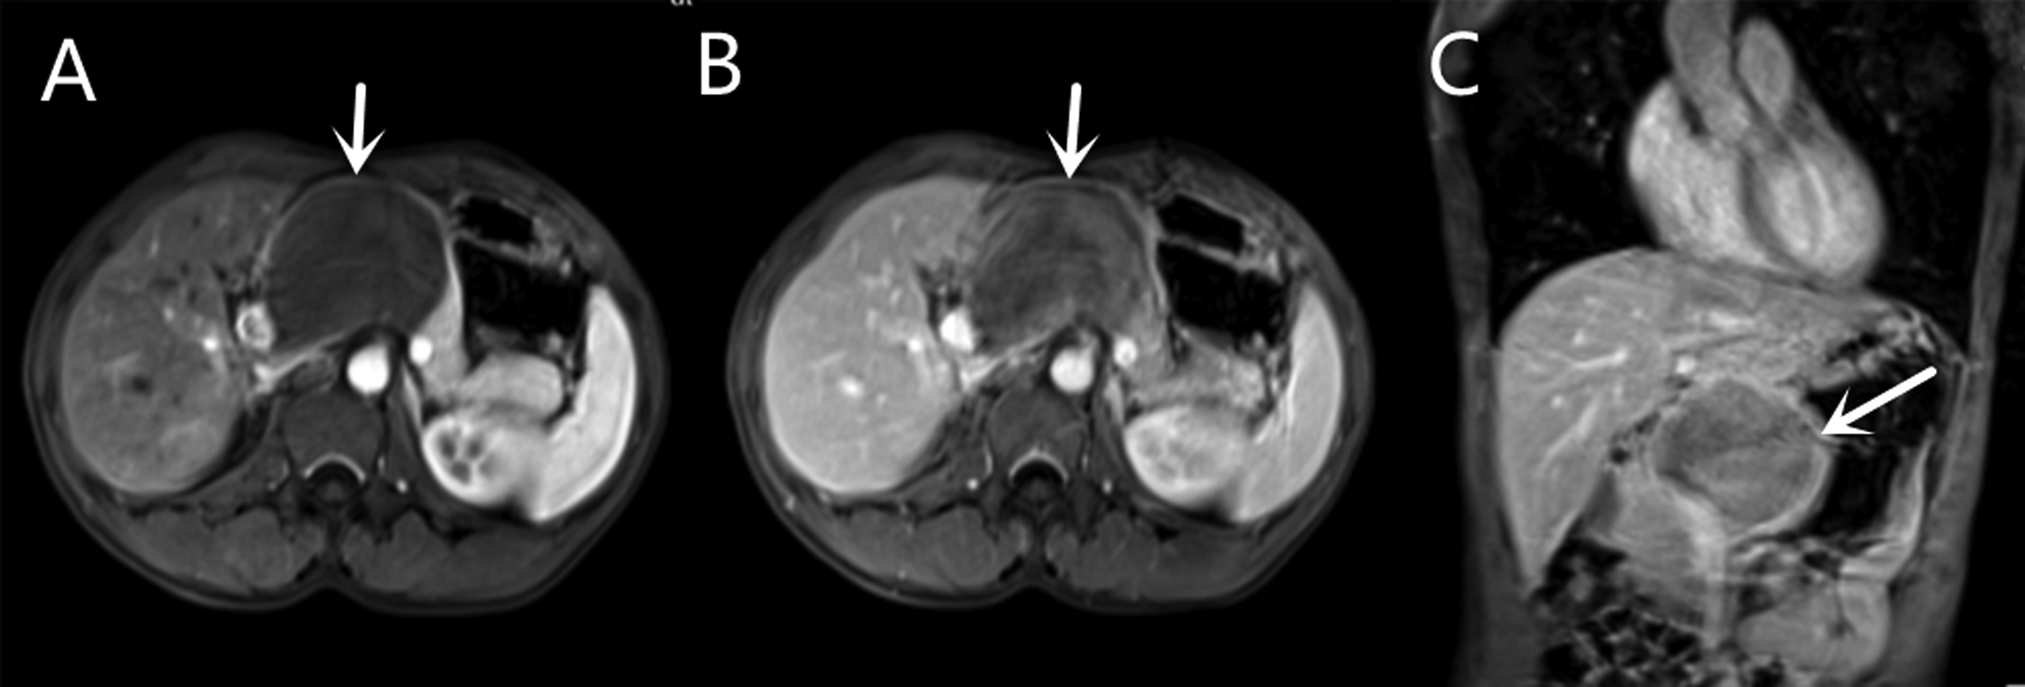

Contrast-enhanced magnetic resonance (MR) revealed an 8.2 × 5.7 cm circular confounding signal mass on the pancreatic neck (Figure 1). It had a slightly higher T1 signal and equal T2 signal with a small patch of high T2 signal inside. Contrast enhancement was heterogeneous high enhancement. The adjacent common hepatic artery and splenic artery were pushed, causing their lumens to narrow slightly, and their local boundaries with the tumor were not clear. The fat space between the splenic vein and the tumor is not clear. The main pancreatic duct and bile duct were not dilated. MR finally considered pancreatic malignant cystadenoma or solid pseudopapillary tumor (SPT). Two-dimensional ultrasonography revealed a slightly weaker echogenic mass of approximately 8.6 × 6.4 cm in the pancreatic neck body area, with clear boundaries, clear capsules, heterogeneous internal echoes, and small hypoechoic areas (Figure 2A). CEUS showed rapid and high enhancement at the margin and equal enhancement at the interior of the mass in the arterial phase. In the parenchymal phase, the overall enhancement was low. CEUS considered mostly SPT (Figures 2B,C).

Figure 1

Contrast-enhanced magnetic resonance (MR) of a mass on the pancreatic neck-body. (A) T1W Cross-sections MR in arterial phase. (B) T1W Cross-sections MR in portal phase. (C) T2W Axial MR in arterial phase.